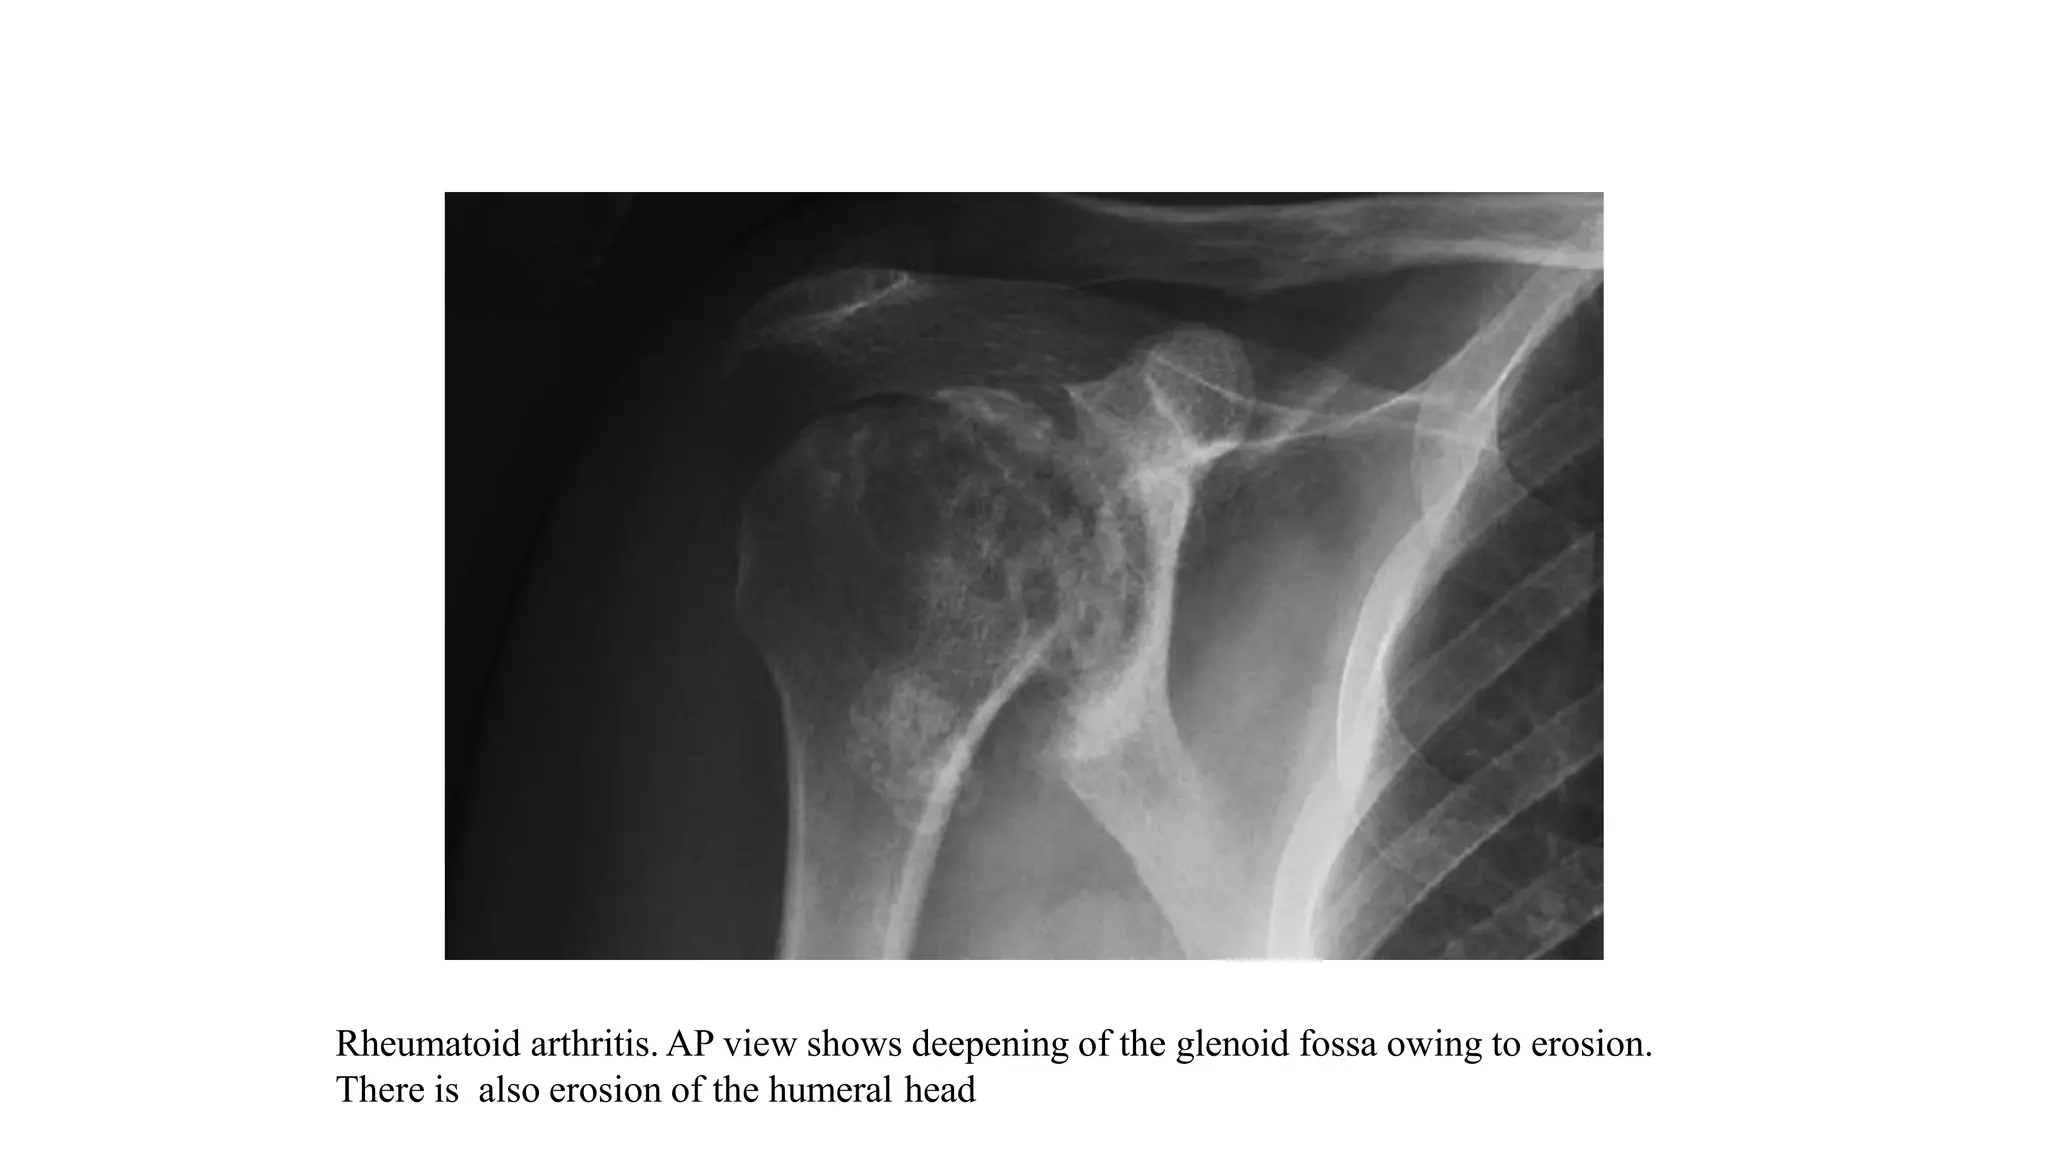

1. RHEUMATOID ARTHRITIS

• The radiographic findings of RA of the shoulder consist of

 periarticular osteopenia

 marginal erosions develop at the bare area (the superolateral aspect of the humeral head adjacent to the

greater tuberosity) where articular cartilage is thin.

 uniform cartilage space narrowing in the absence of osteophytes

 subchondral sclerosis and bursitis.

• As the disease progresses, there is concentric erosion of the glenoid accompanied by medial migration of

the humeral head.

• Atrophy and tear of the rotator cuff with attendant superior migration of the humeral head may follow and

erosion and thinning of the undersurface of the acromion can result.

• The resulting juxtaposition of the medial humeral shaft and the inferior glenoid eventually produces

a notch like defect of the humerus that predisposes to pathologic fracture.

Rheumatoid arthritis. AP radiograph of shoulder demonstrates numerous marginal erosions of proximal

humerus, involving medial aspect of humeral head (arrowheads) and medial aspect of proximal humeral shaft

(long arrow). In addition, there are erosions and tapering of distal clavicle (short arrow).

Rheumatoid arthritis. AP view shows deepening of the glenoid fossa owing to erosion.

There is also erosion of the humeral head